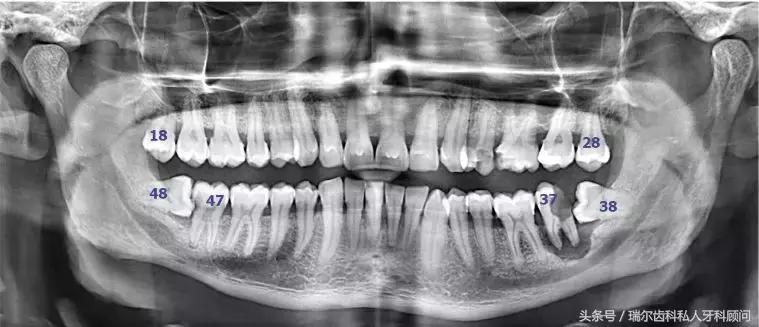

智齿是人类的第三磨牙(从中间门牙往里数第八颗就是),一般在20岁左右萌出,这时候人的生理、心理发育趋于成熟,所以俗称为“智齿”。

一颗不受宠的牙齿,就没有人在意它长成什么样子了,如果它能不卑不亢,像正常牙齿一样,整整齐齐长出来,或者干脆不长了,那都是你的幸运。(一般而言,智齿有上下左右对称的4颗牙,但有人少于4颗甚至没有,极少数人会多于4颗,萌出时间也有差异,有人四五十岁才长,有人终生不长)

当你觉得自己没有智齿的时候,千万别高兴太早,有可能,你的智齿只是被埋在牙槽骨里了而已,我们肉眼看不到,在他们搞出事情之前,想要发现它们需要拍牙片。而且这种躲在暗处,搞破坏于无形的智齿才最可怕,所以,每年定期做好口腔检查能花小钱办大事,就像体检一样,防患于未然。